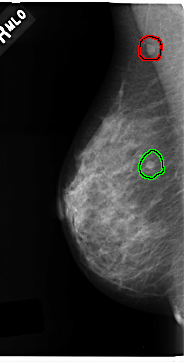

C_0212_1.RIGHT_MLO

FILE: C_0212_1.RIGHT_MLO.OVERLAY

TOTAL_ABNORMALITIES 2

ABNORMALITY 1

LESION_TYPE MASS SHAPE ROUND MARGINS CIRCUMSCRIBED

ASSESSMENT 4

SUBTLETY 5

PATHOLOGY MALIGNANT

TOTAL_OUTLINES 1

BOUNDARY

ABNORMALITY 2